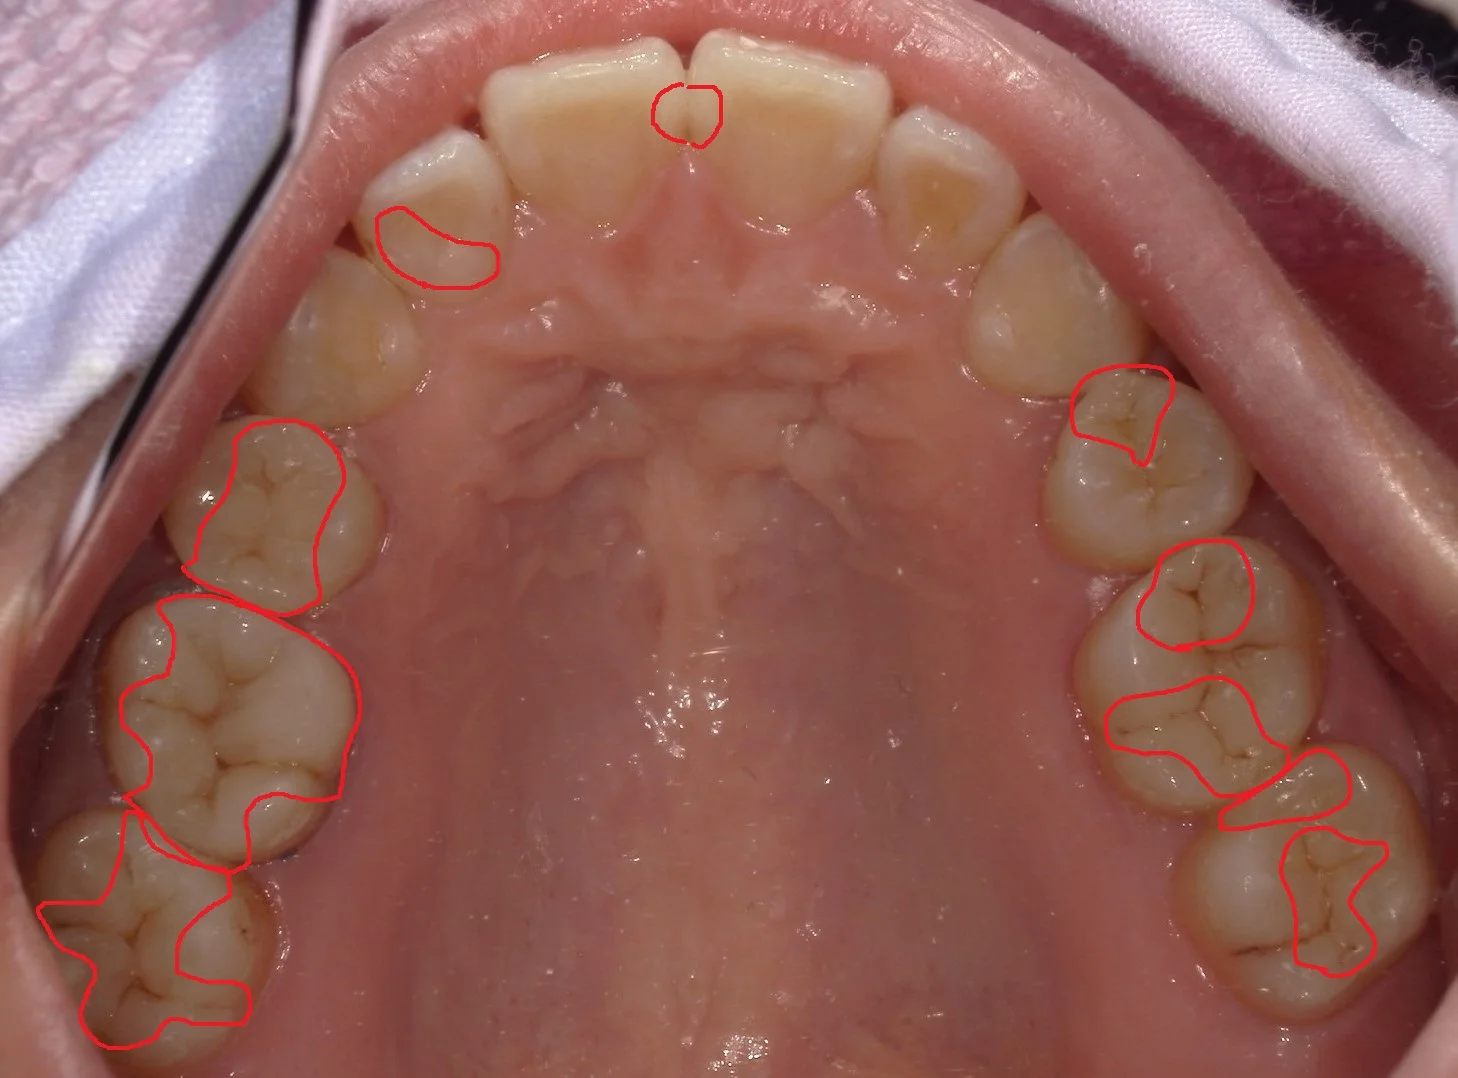

さて、この上下の歯のどこをどこを治療したでしょうか・・・!!

正解は下の方で・・・!

正解はこんな感じですヽ(゚∀゚)ノ パッ☆

計4回で治療終了まで行きました!